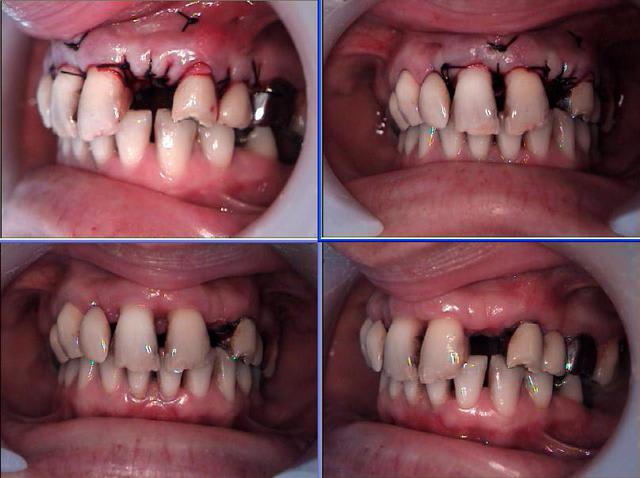

Céramik comme promis Ma réponse en image 2ans après

3 Rx le jour de la POSE de la dent

4 La dent le jour de la pose

7 La dent 2ans après